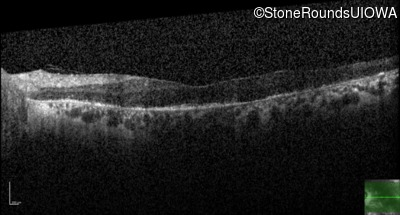

Age at visit: 53 years

OD OS